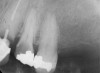

In treatment planning, the decay rate of the patient’s teeth, including the endodontic status of the individual tooth, becomes an important factor when considering long-term outcomes. In the pictured case (Figure 5), tooth No. 11, which previously had been treated endodontically, had recurrent decay and tooth No. 12 had advanced decay with endodontic involvement. In less than 30 days, recurrent decay that reaches the endodontic fill through a leaky restoration (temporary or not), ill-fitting crowns, or broken fillings can re-infect the entire length of the root canal system in a previously endodontically treated tooth.22 Therefore, saving a previously endodontically treated tooth, as in this case, may involve endodontic re-treatment, which can be a deciding factor for tooth preservation.

Figure 5  Recurrent decay of teeth Nos. 11 and 12. Note the proximity of the decay on both teeth to the osseous crest.

Figure 5